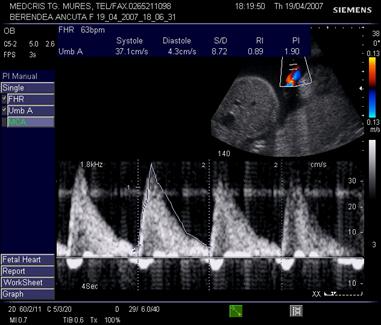

4.Examenul DOPPLER

Aplicatia Doppler a ecografiei permite evidentierea deplasarii hematiilor in sistemul cardiovascular. Christian Doppler in 1842 a descris principiul fizic: daca o unda este reflectata de un obiect in miscare, frecventa undei reflectate e influentata de viteza reflectorului mobil.

In obstetrica se utilizeaza de obicei asocierea Doppler color (CD sau CFM) pentru orientarea in sistemul vascular, dupa care se introduce fereastra doppler pulsat (pDopp).

Indicii observati in cursul explorarii Doppler, care se utilizeaza cel mai frecvent sunt:

Indice de pulsatilitate IP = S - D /M (S - sistola, D - diastola, M = viteza medie in cursul ciclului cardiac).

Indicele de rezistenta placentara Pourcelot (IR)

IR = S - D/S. Se utilizeaza in artera ombilicala si artera cerebrala medie.

Doppler pe artera ombilicala

Daca fasciculul Doppler ("poarta") este bine centrat, sunetul este optim si spectrul este caracteristic pentru artera din cordonul ombilical. Linia de baza trebuie sa separe fluxul arterial de cel venos.

Derularea benzii cu spectrul Doppler va "curge" pana cand exista parametrii de calitate:

sunet caracteristic

minim 5 cicli consecutivi, identici, bine conturati, deasupra liniei de baza

fluxul venos continuu este sub linia de baza